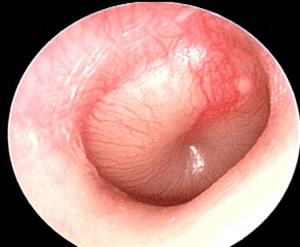

Diagnostika. Otoskopuojant matomas paraudęs, paburkęs ir išpūstas būgnelis, sumažėjęs jo judrumas, nesimato būgnelio anatominių struktūrų. Mažiems vaikams skausmingas krampslio (tragus) spaudimas. Vaikai būna neramūs, nevalgo, dažnai ir be priežasties verkia. Tiriant ligonio klausą beveik visada nustatomas jos susilpnėjimas. Kamertoniniai tyrimai: Weberis lateralizuoja į pažeistą pusę, Rinne neigiamas uždegimo pažeistoje pusėje. Timpanometrija pažeistoje pusėje būna B tipo, audiogramoje nustatomas garsą pravedančios sistemos pakenkimas, kartais kai pažeidžiamas ir klausos nervas – mišrus klausos pakenkimas.